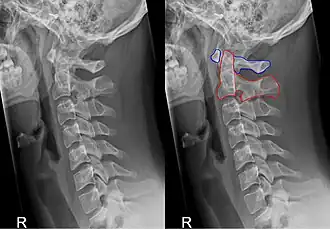

Membrana atlantooccipitalis posterior en ligamentum atlantooccipitale. (Axis in het midden) | ||||